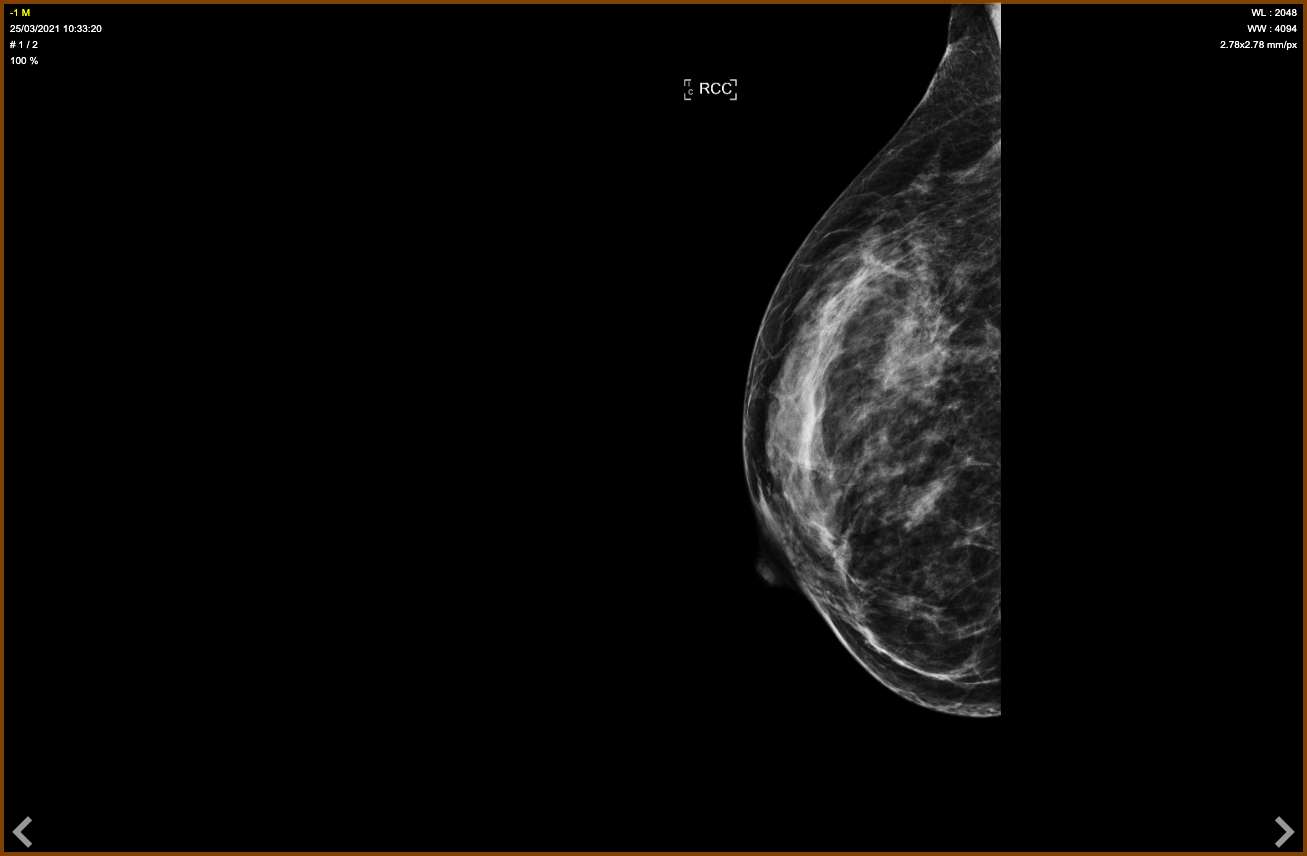

47-year-old woman, screening mammogram.

A cluster of 18 mm amorphous microcalcifications projecting on the right pectoral muscle BI-RADS 4b, difficult to see.

Macrobiopsy under stereotactic control with radiography of the specimens.

Results: Fibrocystic mastopathy associated with focal atypical ductal hyperplasia.